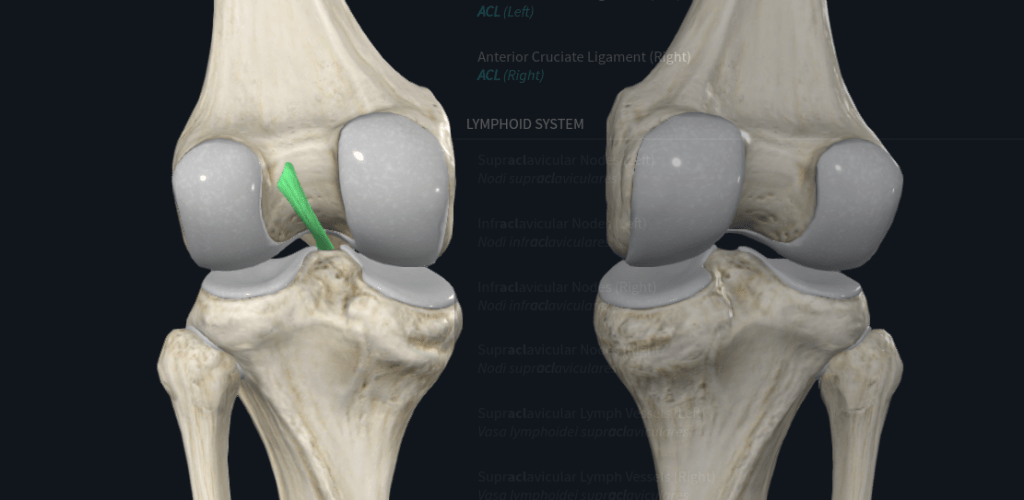

ACL injuries for kids have become an epidemic in the States. Adolescent girls suffer the most, in sports that include a lot of unpredictable cutting like soccer, basketball, etc.

My understanding of the literature as to why this is happening, can be distilled down to a lack of structural balance.

Every pound added above the waist corresponds to an exponential weight impacted at the knee. We experience 2x the impact at the knee just walking flat ground. So if a 150 pound athlete is dynamically moving, jumping, twisting, stopping…it’s just common sense that the demands that are trying to pull that knee apart are incredibly high!